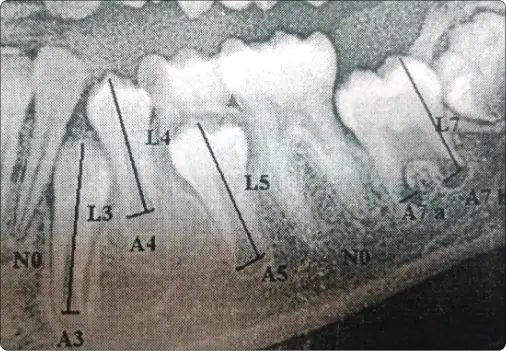

As a part of pre-clinical training exercise in Forensic Odontology, various dental age estimation methods were demonstrated to First year post graduate students. Various radiographic methods were used by the post graduate students to examine age dependent changes in dentition and derive the dental age of the studied population group.The following methods were utilized in the training program:

1. Demirijian’s method:

Panoramic radiographs were used to assess mandibular left side teeth from central incisor (31) to third molar (38) for age estimation. The radiographic development stages of the teeth were denoted and different maturity scores were provided for males and females. The total maturity score obtained from all the teeth was substituted in given regression formulas to derive dental age.

2. Modified Demirijian’s method:

3. Cameriere’s method:

Panoramic radiographs were used for the measurement of open apices of seven permanent left mandibular teeth and dental age was estimated by using Cameriere’s regression formula.

4. Kvaal’s method:

Several measurements like pulp-root length, pulp-tooth length, tooth-root length and pulp-root width of six suggested teeth were made on peri-apical radiographs. The mean value of the measured ratios were derived and substituted in the given regression formulas to derive dental age.